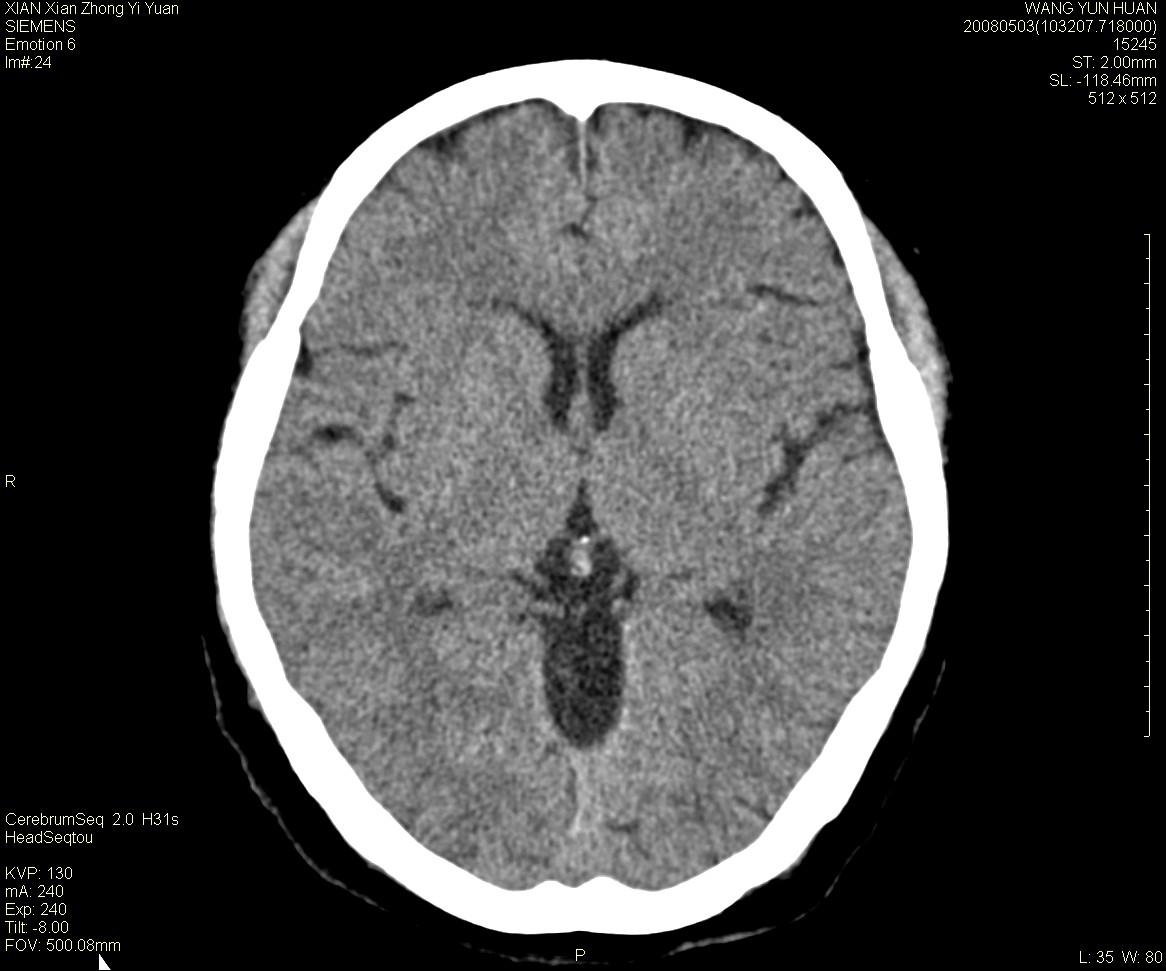

标题: CT13219:(补充强化)请会诊,患者女,60岁,头晕,大家看 [打印本页]

标题: CT13219:(补充强化)请会诊,患者女,60岁,头晕,大家看

病灶显示轻度强化,ct增加4hu左右,大家看是什么肿瘤.

强化后动脉期及延迟2分钟,五分钟图像

小脑蚓部囊型肿块,内有实性结节及钙化点。增强后囊壁及结节轻度强化。

考虑蚓部星形细胞瘤(ⅱ级可能性大)。

小脑蚓部肿块,周围无明显占位效应及水肿带,增强轻度强化,考虑低分级星形细胞瘤。